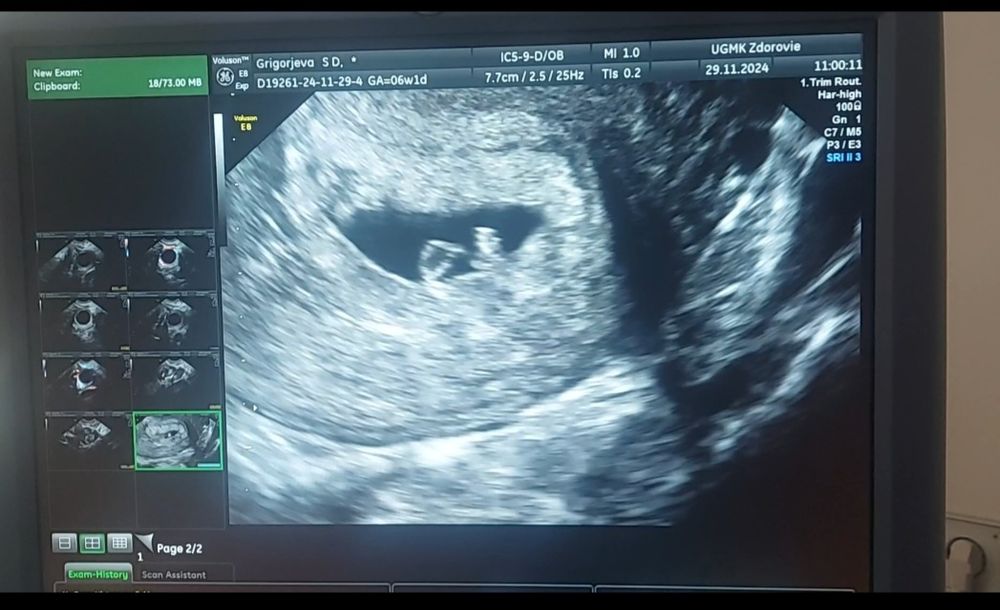

Светланка в Зачатие год Сходила второй раз на узи) УЗИ Увидели сердцебиение, дали послушать ❤️Срок соответствует М, 6 нед 1 день. На 2 фото справа эмбриончик, слева желточный мешочек. Посмотрите еще 20 записей на эту тему Лучший ответ Яна Поздравляю 🙏 29.11.2024 Ответить Отменить Ответить Доминантный фолликул 17 мм Первое узи, эмоции Чаты Беременных Выберите чат: Январята-2026 Февралята-2026 Мартята-2026 Апрелята-2026 Майчата-2026 Июнята-2026 Июлята-2026 Августята-2026